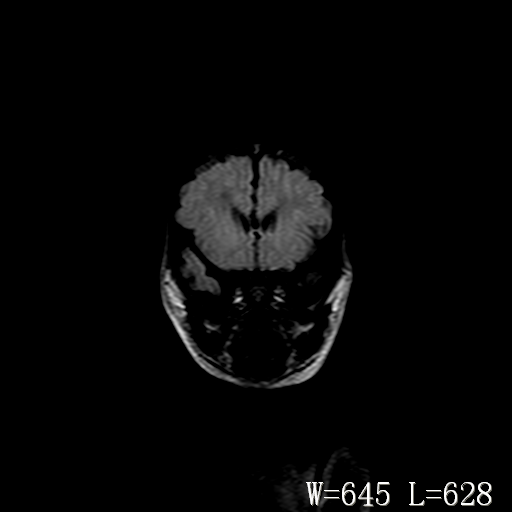

脑干形态欠规则,信号增高,不知怎么解释?

脑干背侧面t1高信号是,新生儿正常已经髓鞘化好的部位